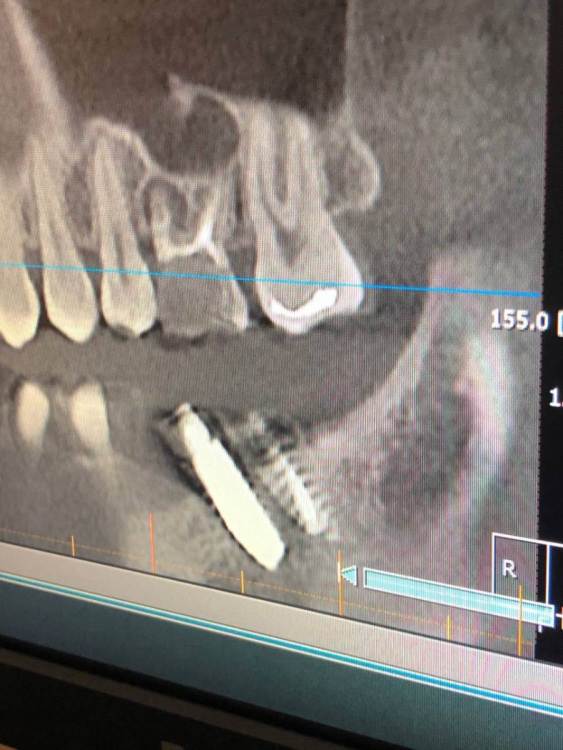

Фото 7,8 - Также была проведена резекция кисты 5 зуба снизу , с коронкой , и установка 7 импланта в качестве антагониста верхней 7 . Одной операцией . Коронка оголилась , швы сняли на 3 день .. доктор также утверждает что в дальнейшем будет все хорошо , зарастет . Также очень смешает внешний вид десны , десна стала волной даже на 6 ..